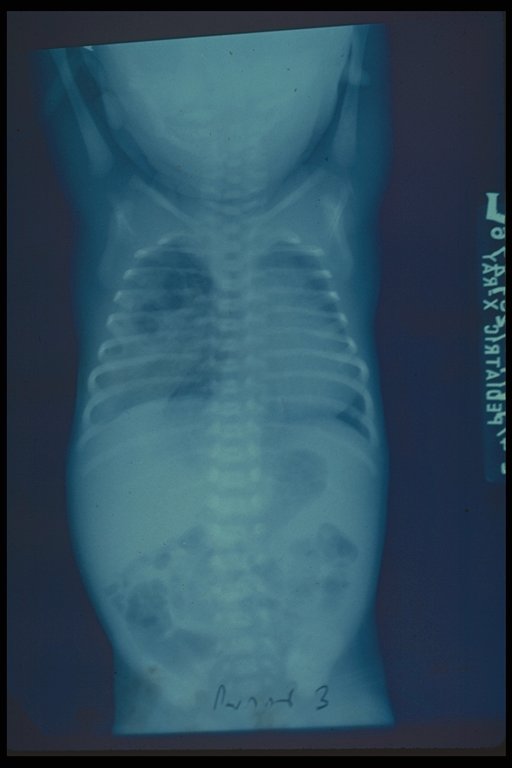

Chest X-ray finding in a case of cystic adenomatoid right lung